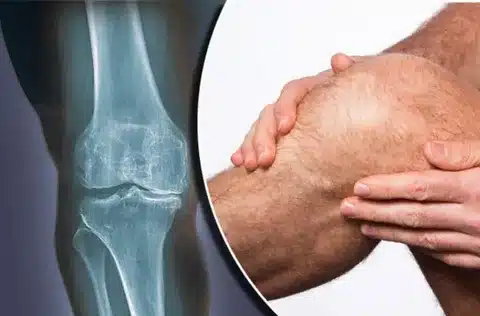

سلام به شما همراهان گرامی! آیا تا به حال از خود پرسیدهاید “چرا مفصل زانو درد می کند؟” این مقاله از گروه ارتوپدی سامان تلاشی است برای پاسخ به این سوال مهم و آشنایی شما با علل و درمان های درد زانو. زانو یکی از بزرگترین و پیچیدهترین مفاصل بدن است که نقش مهمی در حرکت و پایداری ما ایفا میکند. درد زانو میتواند ناشی از عوامل مختلفی باشد و زندگی روزمره را مختل کند. در این مقاله، با بررسی علل شایع درد زانو، روشهای تشخیص و درمان، و نکات پیشگیری، به شما کمک میکنیم تا از این درد خلاص شوید و به زندگی فعال خود بازگردید.

چرا مفصل زانو درد می کند؟

این سوالی است که ذهن بسیاری از افراد را به خود مشغول کرده است. عوامل مختلفی میتوانند باعث درد زانو شوند. برخی از این عوامل عبارتند از: